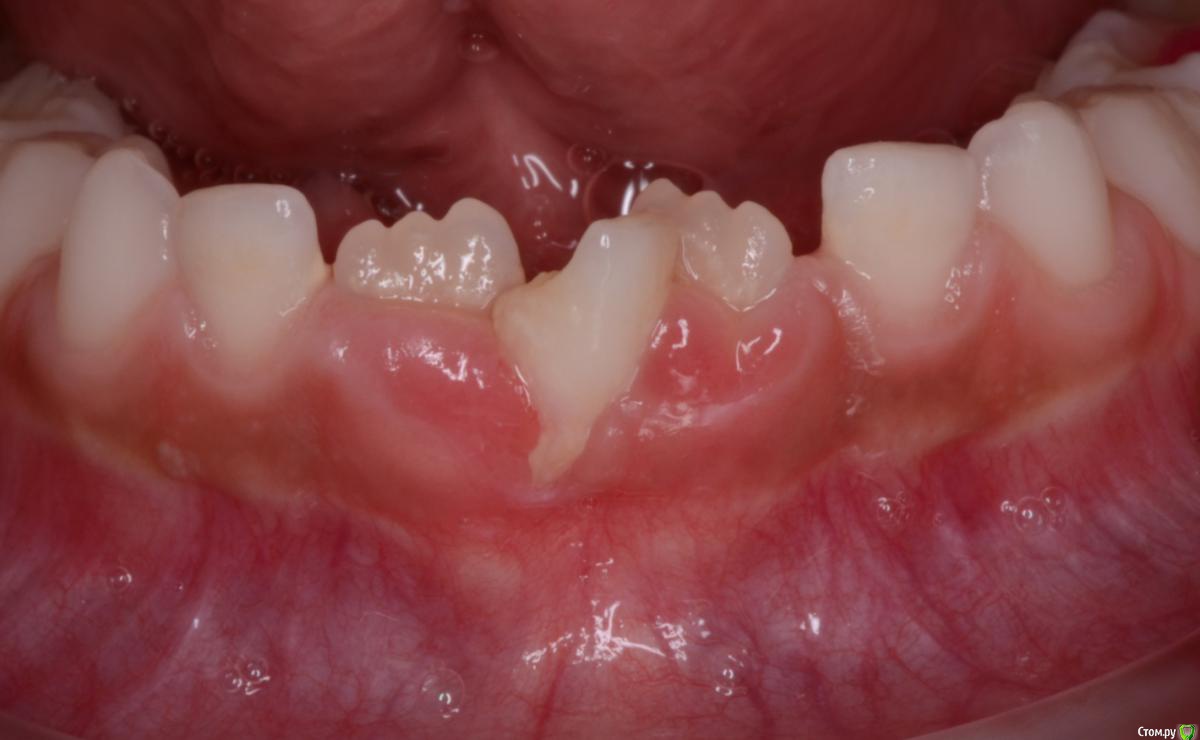

CRAZYDUCK Опубликовано 11 февраля, 2020 Автор Поделиться Опубликовано 11 февраля, 2020 Физиологическая смена зуба , восстановленного ранее стандартной коронкойtrim.EAB9F42F-C9D4-43B2-B836-171869F3A129.MOV 4 Ссылка на комментарий

CRAZYDUCK Опубликовано 14 февраля, 2020 Автор Поделиться Опубликовано 14 февраля, 2020 Красивое красное фото ! Резорбция корня временного Резца почти полная , но уходить он не хочет . Удалила и жлеммна осмотр через месяц . Ссылка на комментарий